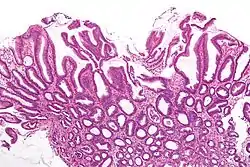

| Micrograph of a reactive gastropathy. H&E stain. | |

- Foveolar hyperplasia (black arrow), as a tortuosity in the "neck" region of the gastric glands.

- Scant or minimal inflammatory cells (white arrow), i.e. lack of large numbers of neutrophils and plasma cells..

- Smooth muscle hyperplasia in the lamina propria (in black oval).

The diagnosis is by examination of tissue, e.g. a stomach biopsy.